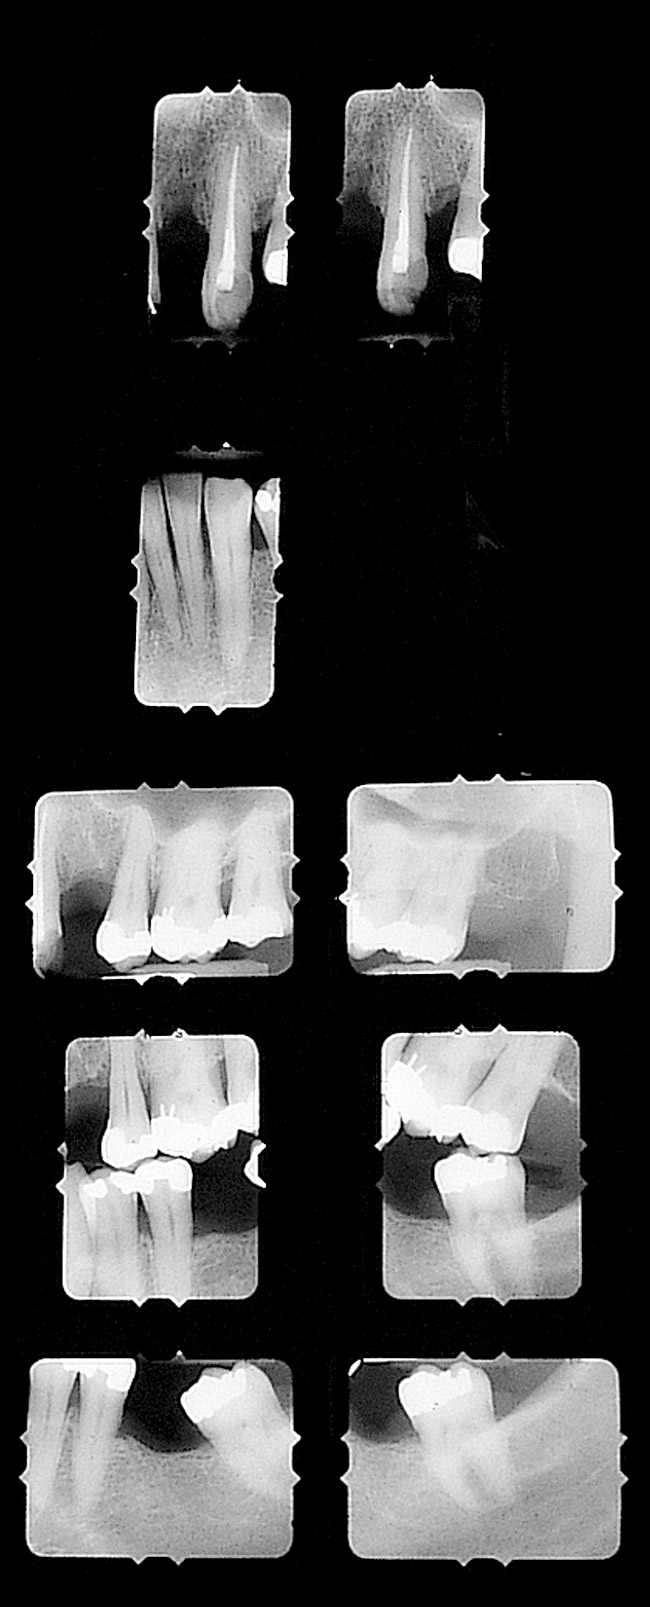

Figure 16  Preoperative radiographic view, right side.

Figure 16

Figure 17  Preoperative radiographic view, left side.

Figure 17